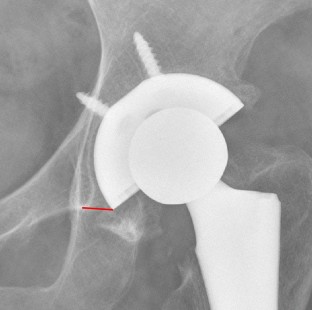

(4) In the dots_LU, a point closest to the d_LU from the boneedge_LU was found, named A;

(5) In the dots_MD, a point closest to the d_MD from the teardrop_BT was found, named B;

(6) The acetabular cup circle passed through A and B, so the acetabular cup center O was located on the mid-perpendicular line of AB; for the hemispherical acetabular cup, the ∠AOB was 180 − (18 + median_th_MD), for the sub-hemisphere/super hemisphere acetabular cup, if the center angle of the acetabular cup was angle_cup, then ∠AOB was angle_cup − (18 + median_th_MD); the diameter of the acetabular cup was calculated as d_cup_templating = L/sin(∠AOB/2), where L was the distance between AB. In addition, the coordinates of the center O of the acetabular cup was calculated and named as center_cup_templating; (Fig. 8).

If it is known that a circle passes through two points A and B, it can be known that the center O of this circle is located on the perpendicular line of the line segment AB. If we also know ∠AOB, we can determine the position of the center O and the radius of this circle. In fact, there are two solutions for the circle center, which are located on both sides of the line segment, but considering the application scenario of the pelvic X-ray, the circle center O must be positioned below the line segment AB, so there is only one reasonable solution. To calculate the radius of the cup circle, we need to first determine A, B, and ∠AOB, and then determine O, and then the length of the AO is the radius of the cup.

On the AP X-ray of the pelvis, A is the lateral superior intersection of the cup and the inner wall of the acetabulum. The distance between it and the lateral edge of the acetabulum is d_LU. By measuring the d_LU on postsurgery X-ray of all 406 cases, the median of d_LU is obtained. When templating a new preoperative AP X-ray of the pelvis, as long as we know the coordinates of the lateral edge of the acetabulum and the contour of the nearby acetabular edge, combining with the value of median_d_LU, the ideal position of A can be estimated (A is located on this contour and its distance from the lateral edge of the acetabulum is median_d_LU). In a similar way, the ideal position of B, the medial inferior intersection of the cup and the inner wall of the acetabulum, can also be obtained.

By measuring the th_MD on postsurgery X-ray of all 406 cases, the median of this angle can be obtained (median_d_MD); the lateral uncoverage should not exceed 20%. It can be known that the average coverage ratio is 10%, then the ideal angle on the lateral side should be 180° × 10% = 18°, so the ideal ∠AOB should be equal to 180° − (18 + median_d_MD).

In this way, A, B and ∠AOB are obtained, and then the position and radius of the cup can be calculated.